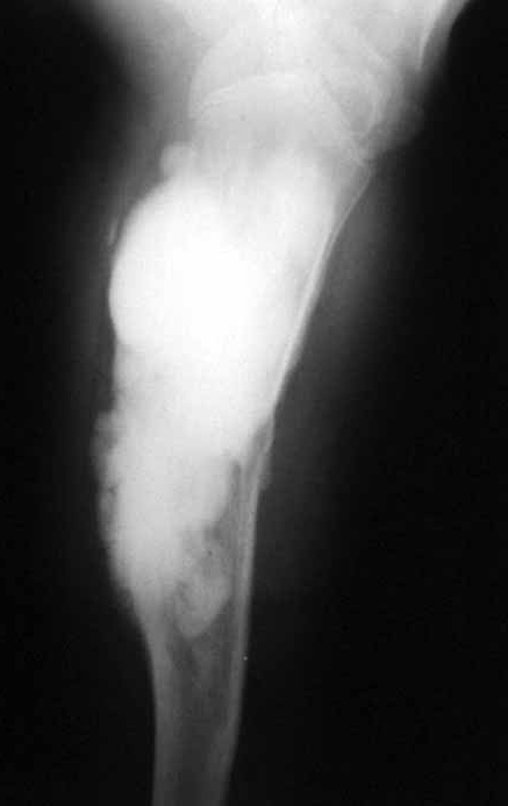

Osteossarcoma com Metá Pulmonar. Paciente nascida em 07/06/1976, é atendida em 1987, com onze anos de idade, com antecedente de duas intervenções cirúrgicas prévias, de curetagem de lesão no úmero proximal esquerdo, havia um ano.

O laudo anátomo patológico diagnosticava tratar-se de osteossarcoma do tipo paraosteal, que devido à manipulação cirúrgica havia invadido o canal medular e já apresentava dois nódulos metastáticos para o pulmão, figuras 1 à 5.